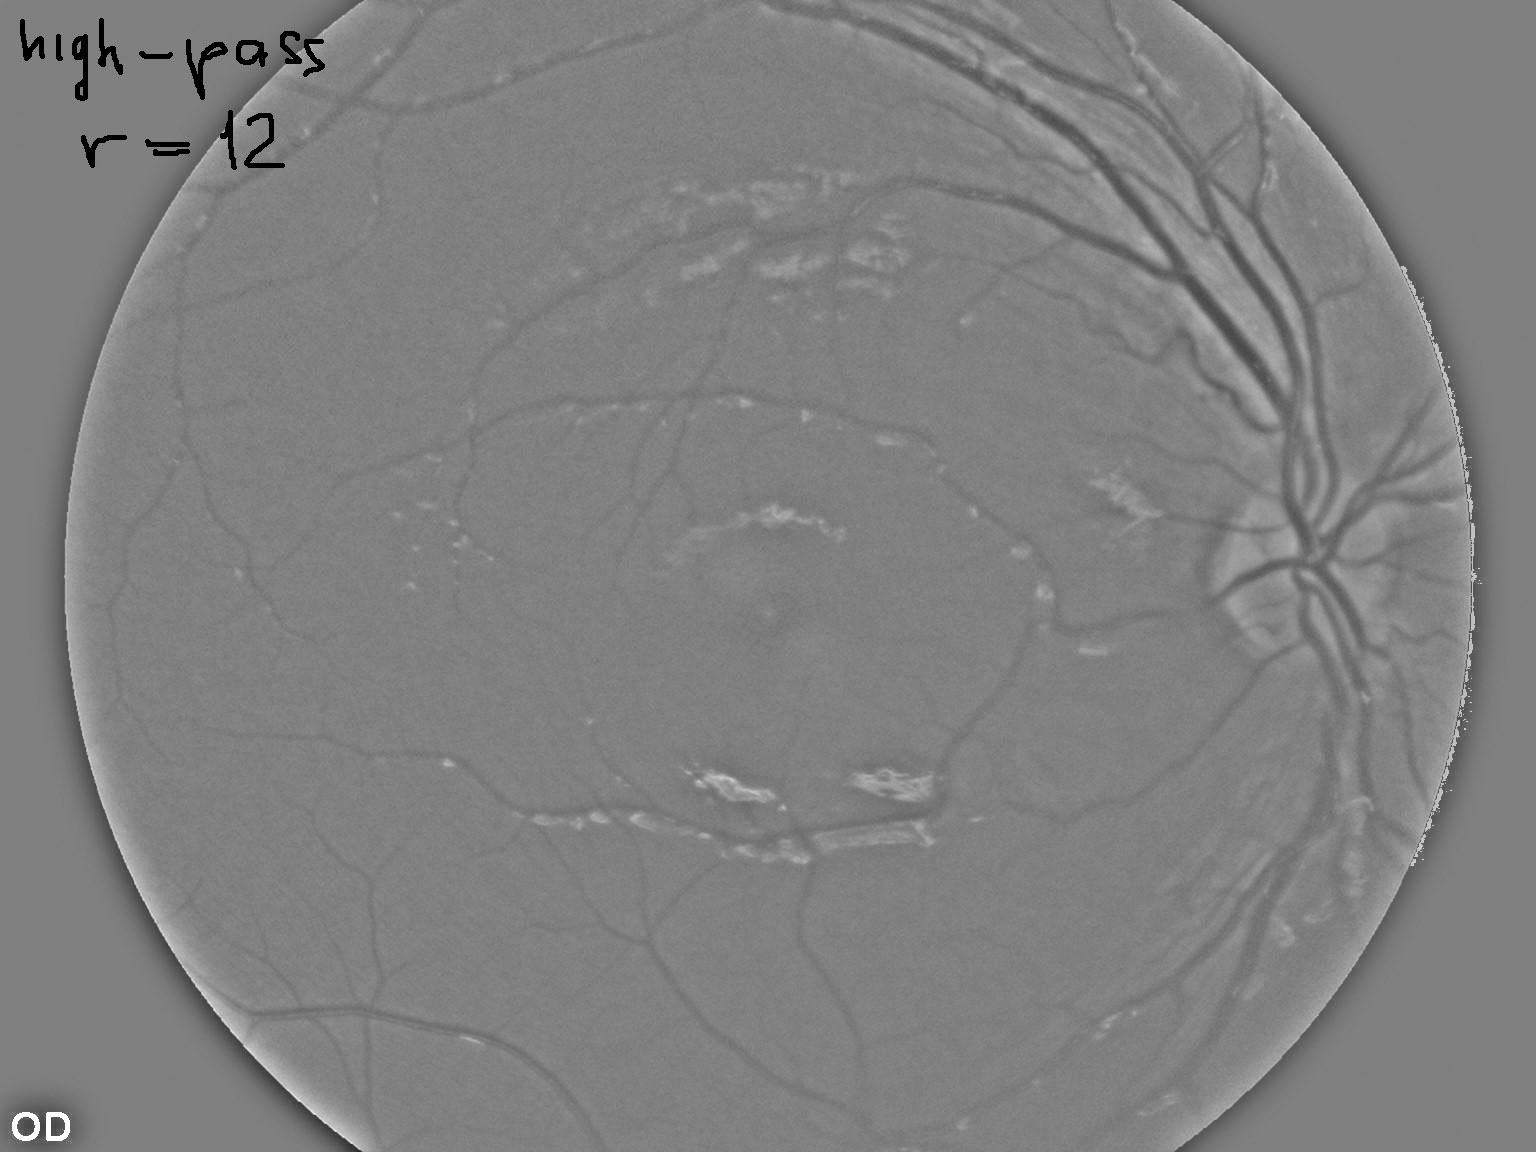

如何:高通(图像减去高斯平滑与西格玛12),然后阈值(126),然后小目标抑制(小于300个像素的对象被删除)?

(我用了你的上一张照片)